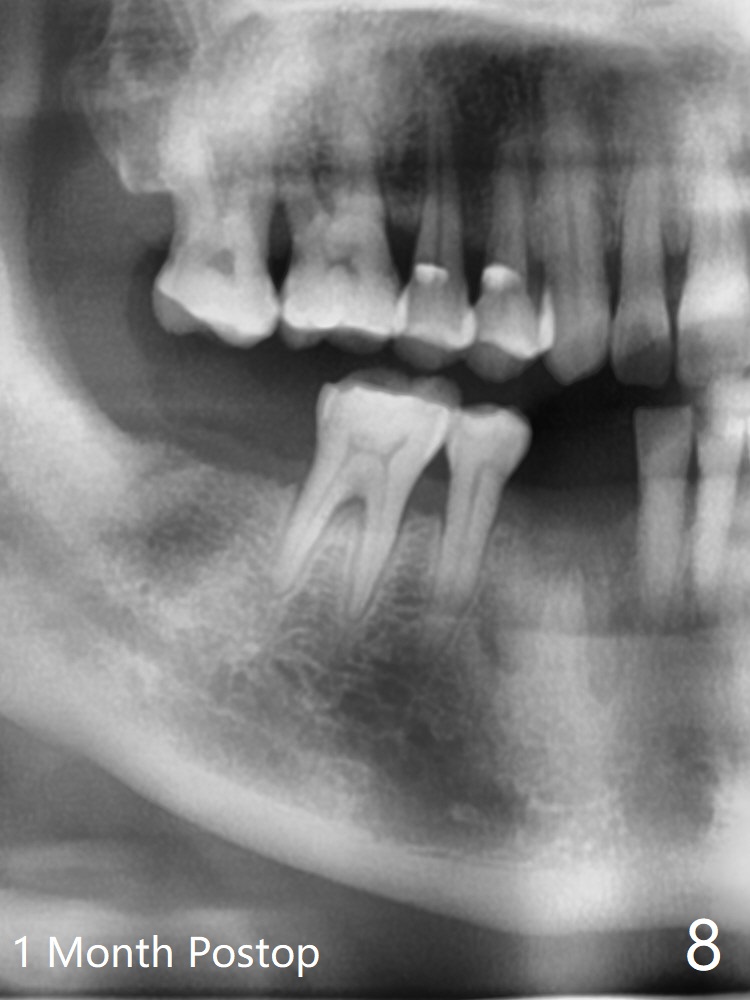

66岁男1.5年前来诊所拍摄全景片(图一),似乎27,28号牙还能保留,今天突然回来,主诉27、28区疼痛瘘道,商量决定先拔除27,28,32及右下深洗。拔除32号牙时发现它接近31区(将要植牙),必须植骨(近中部分(远中塞入胶原塞)),27,28颊侧骨板缺失(大量肉芽组织),植骨理所应当,而且必须拼命推压,但愿推到颊侧骨板,细的皮质骨没有压制感,非要加入粗的松质骨皮质骨,一张12x12毫米胎盘膜剪成两片覆盖27/28和32拔牙窝,4-0 PGA缝线固定,拍摄术后半侧全景片后(图二 (*:骨粉)),使用牙周敷料保护伤口。术后一个月27,28号牙位骨粉保持原位,而且颊侧骨板好像已经重建(图八,十一,九),似乎能植入两个植体(图十,十二)。